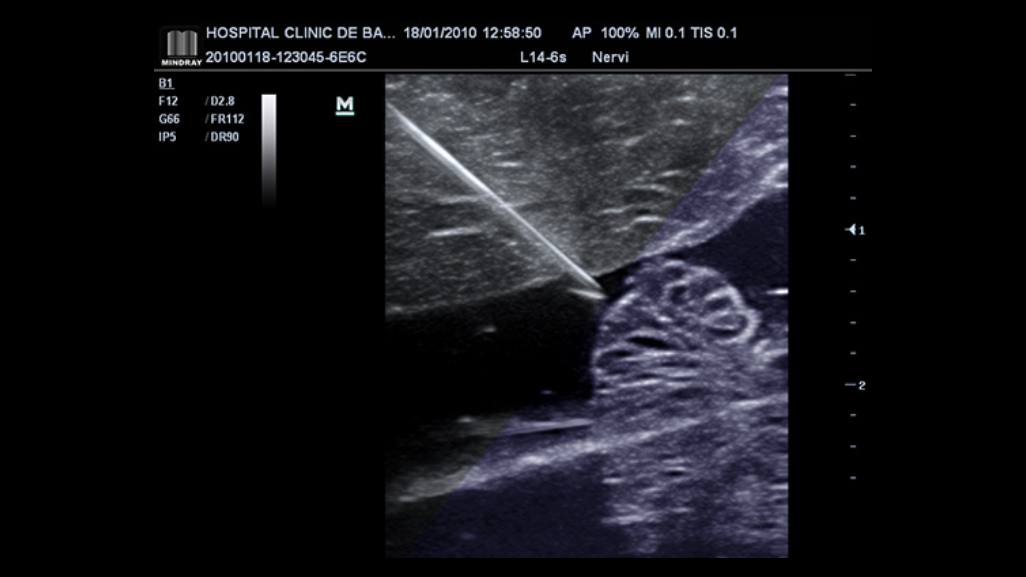

iNeedle

The totally new iNeedle is able to recognize and adapt the puncture angle automatically, enhancing both needle tip and pathway clearly.